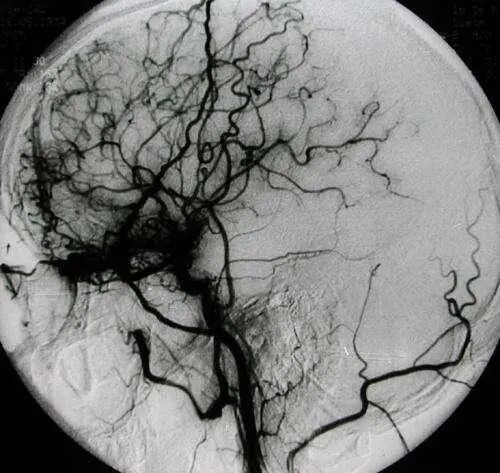

烟雾病是一种病因不明的、以双侧颈内动脉末端及大脑前动脉、大脑中动脉起始部慢性进行性狭窄或闭塞为特征,并继发颅底异常血管网形成的一种脑血管疾病。

由于这种颅底异常血管网在脑血管造影图像上形似“烟雾”,故称为“烟雾病”。